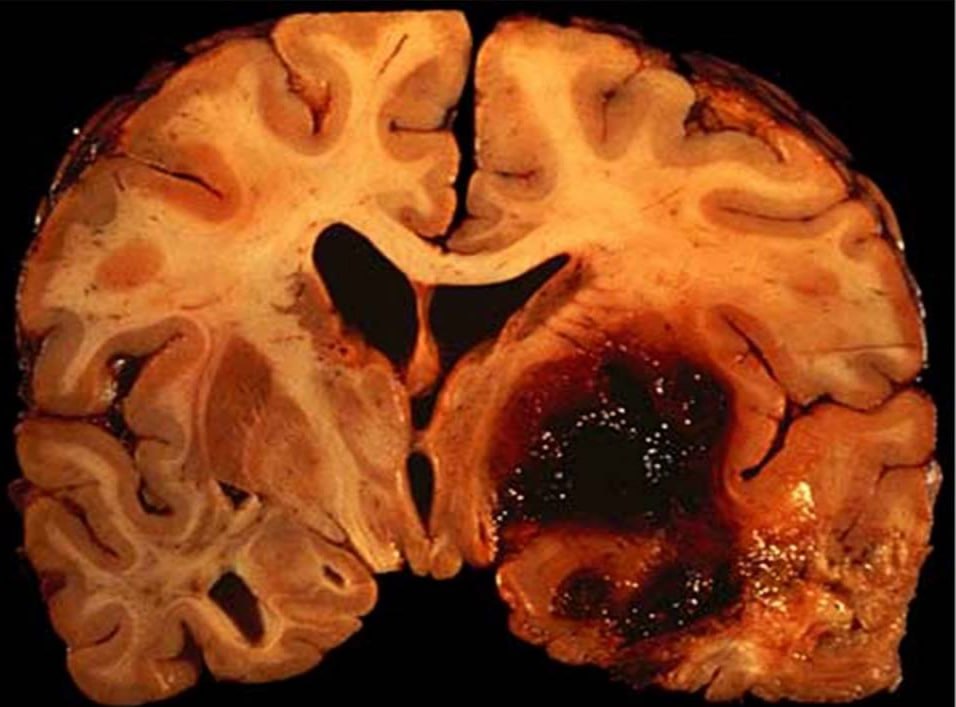

Кровоизлияние в полости черепа.

Это очень серьёзная патология. Пациенту необходима скорая медицинская помощь — излившаяся в полость черепа кровь вызывает повышение внутричерепного давления, что может привести к повреждению нервной ткани.

Кровоизлияние в мозг — это гонка со временем. Счёт идет на минуты. Задача окружающих — немедленно вызвать скорую помощь. Задача врачей — как можно быстрее удалить гематому (часто хирургическим путем) и остановить кровотечение, чтобы спасти мозг и жизнь пациента.